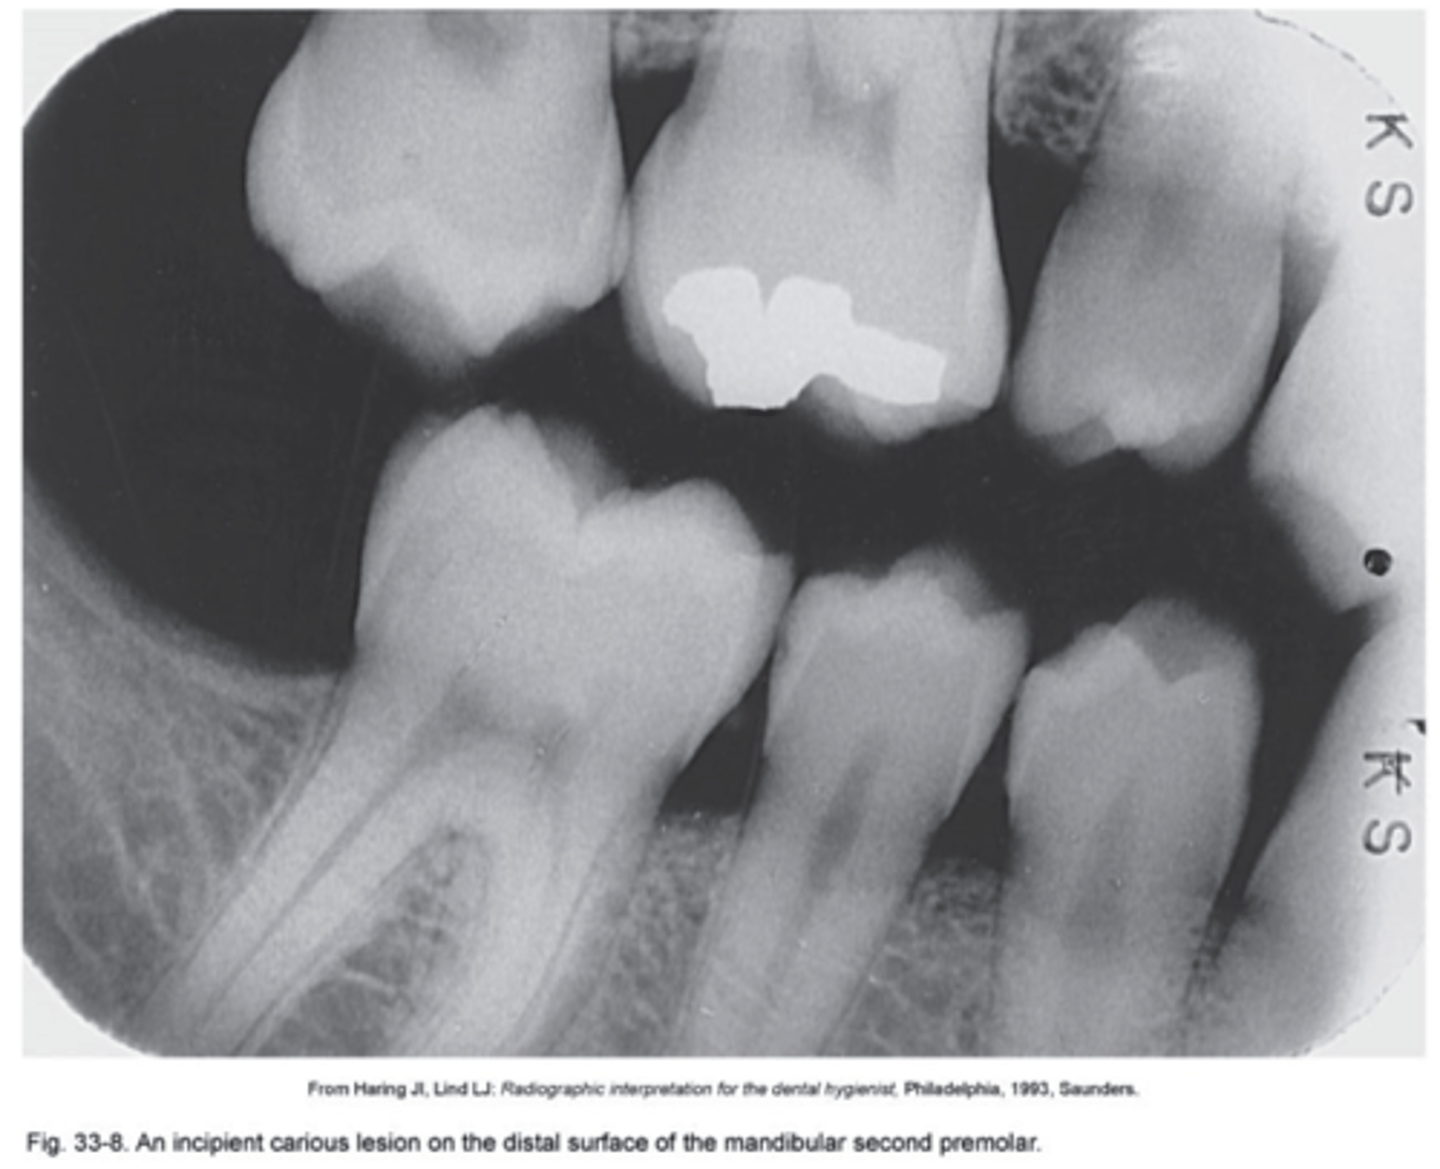

What are Incipient Interproximal Caries?

Extends less than halfway through the thickness of enamel. Class I